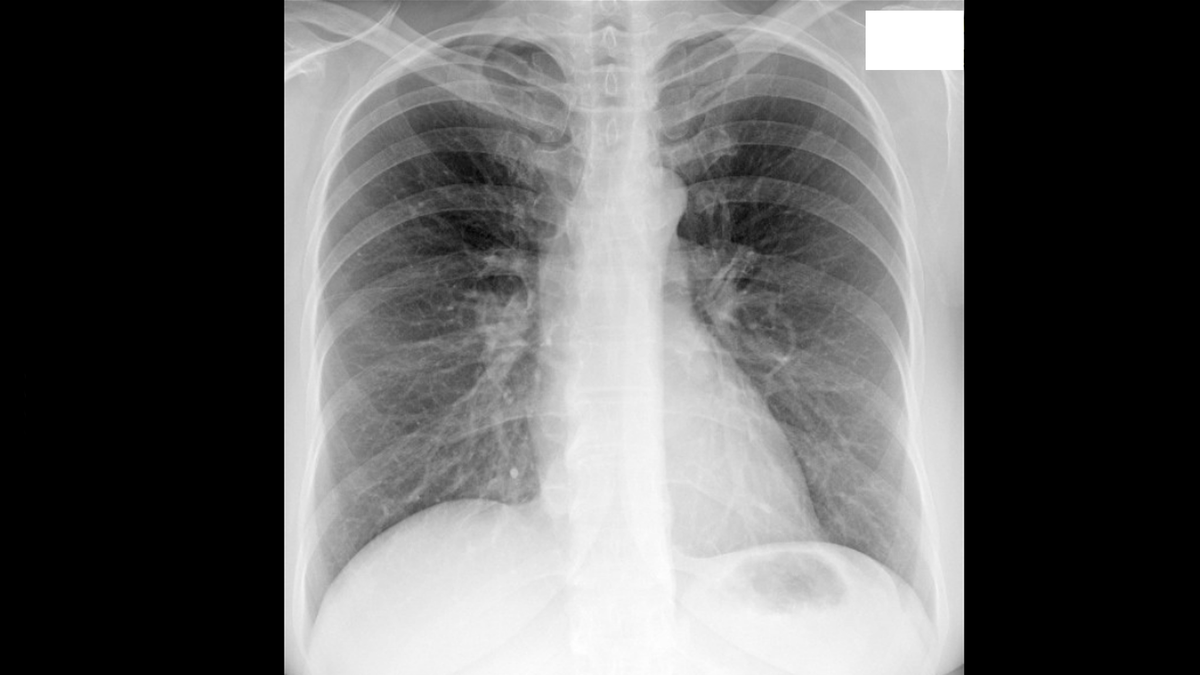

Начало истории было в октябре 2024 года, в момент очередной диспансеризации, когда флюорография неожиданно показала наличие больших образований в легких, причем множественных. Год назад у пациентки ничего подобного не было.

Прилагаю снимки сделанные при флюорографии. На первом снимке осень 2023 года, а на втором снимке осень 2024 года.

Флюорография. Осень 2023 года.